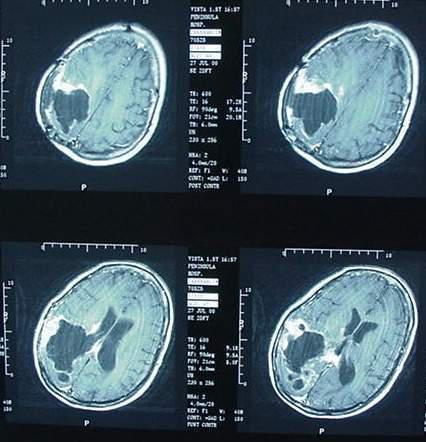

9 ans Tumeur au cerveau La fille de mon amie hier a présenté une paralysie du coté gauche, une perte de motricité et des maux de tête important Le scanner montre une tumeur au cerveau Le pédiatre qualifie la situation de sérieuse Ces tumeurs peuvent commencer dans le cerveau mais, parfois, le cancer peut démarrer dans d'autres organes puis s'étendre au cerveau C'est ce qu'on appelle une tumeur métastatique ou secondaire Les cancers les plus courants comme ceux du colon, du sein, du rein, du mélanome ou des poumons peuvent se métastaser (c'estàdire se propager) dans le cerveau Les tumeurs rhabdoïdes et tératoïdes atypiques sont rares 1 cas/millions/an Extrêmement agressives, le pronostic reste très mauvais environ 25% de survie globale à 2 ans Les tumeurs rhabdoïdes et tératoïdes atypiques (ATRT) sont, quant à elles, dues à l'extinction d'un gène suppresseur de tumeurs appelé SMARCB1 ou INI1, découverte en 1998 par le laboratoire